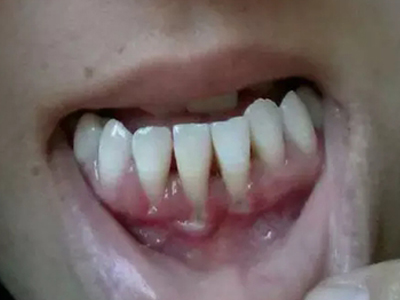

牙龈退缩露出淡黄色牙根图

牙龈退缩患者的牙龈退缩后,淡黄色牙龈明显露出。若进一步发展,易使对应位点的牙槽骨发生骨吸收,可能诱发龋齿、牙龈敏感、菌斑堆积等。